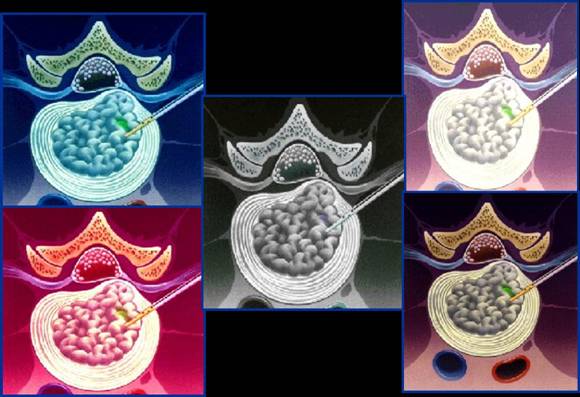

- Tipos de Nucleotomía Percutánea

Tipos de Nucleotomía Percutánea:

Existen varios tipos de nucleotomía percutánea:

Nucleotomía percutánea automatizada: Consiste en un aparato que consta de una consola conectada a una serie de mangueras y aparatos que se introducen a nivel del espacio intervertebral y ejercen un efecto aspirativo en el centro el disco, disminuyendo de esta forma la presión intradiscal.

Nucleotomía percutánea manual o semi-automatizada:

Representa una opción mucho menos traumática, pues los instrumentos son mucho más delgados no sobrepasando los 3 o 4 milímetros a nivel lumbar y algunas veces los 2 o 3 milímetros a nivel cervical. En este caso el cirujano introduce instrumentos muy finos y delicados a través de un pequeño agujero hecho en la piel por donde va a tratar la hernia discal. El agujero de la piel es tan pequeño que no necesita sutura al final del procedimiento.

Nucleotomía percutánea con apoyo artroscópico:

Esta técnica debe realizarse evaluando y seleccionando cada caso individualmente (paciente y tipo de hernia).